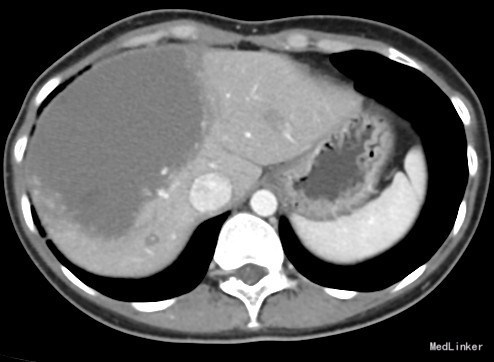

患者女,30岁,主因“发现肝血管瘤18天”以“肝血管瘤”收入院。 病例特点: (1)青年女性患者,慢性起病。 (2)患者18天前于单位体检时发现肝占位性病变,后到顺义区医院就诊,查腹部增强MRI报告:肝血管瘤可能,大小约10cm;脂肪肝;肝囊肿(患者自述,未见报告)。为求进一步治疗就诊我院,以"肝血管瘤"收住院。

肝血管瘤 剖腹探查,肝血管瘤剥除术